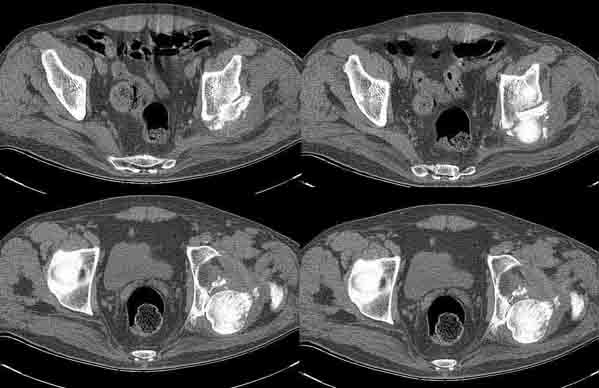

Больной Н. 54 лет. Поступил в подвздошным вывихом левого бедра. После попытки закрытого одномомендного вправления 2 мес. на скелетном вытяжении. На Rg контроле видимость вправления, на КТ - неустраненный вывих. По причине тяжелой соматической патологии открытое вправление и репозицию заднего края выполнить не представляется возможным. Вправление аппаратом внешней фиксации, КТ - этапах вправления - дефект заднего края. Что вы нам посоветуете по дальнейшей тактике?

Больной Н. 54 лет. Диагноз: Закрытый оскольчатый перелом заднего края вертлужной впадины слева, подвздошный вывих левого бедра. Ушиб грудной клетки. ИБС. Стенокардия напряжения. ФКI-II. Постинфарктный кардиосклероз. Артериальная гипертония II степени, риск IV. НI. Состояние после аорто-коронарного шунтирования. Хронический бронхит. ДНI. Травма в результате ДТП. Больной лечился консервативно - закрытое одномоментное ручное вправление, фиксация скелетным вытяжением в течение 2 месяцев. На контрольных обзорных рентгенограммах таза в динамике: головка бедра располагается в проекции вертлужной впадины, суставные поверхности конгруентны. После снятия скелетного вытяжения выполнялся КТ - контроль тазобедренного сустава, на котором обнаружен неустраненный задний вывих бедра. Через 2 месяца наложена передняя тазовая и бедренная опоры. По причине тяжелого соматического состояния не представлялось возможным выполнить открытое вправление вывиха и остеосинтез заднего края. Представлен КТ- контроль на этапе вправления, на котором виден дефект заднего края вертлужной впадины.